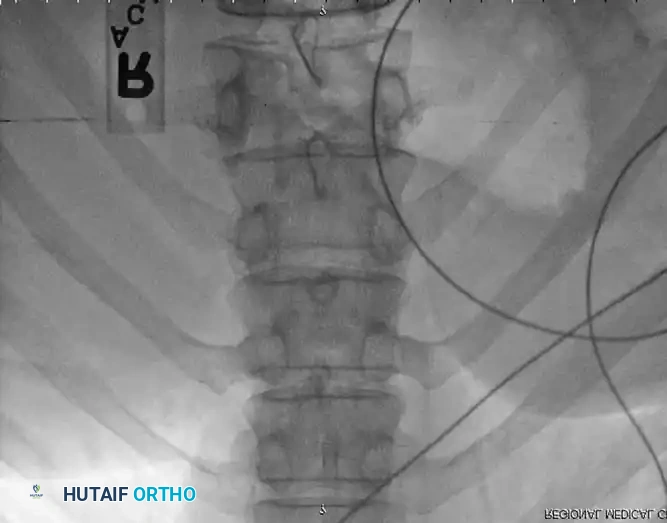

The patient is positioned prone on a radiolucent Jackson table. Neuromonitoring (SSEPs and MEPs) is established. A standard midline posterior approach is utilized, carefully preserving the facet capsules of adjacent uninjured levels.

Pedicle screws are inserted under fluoroscopic or navigation guidance. The trajectory must respect the anatomical convergence of the pedicles, which varies from the thoracic to the lumbar spine.

Following screw placement, rods are contoured to restore physiological sagittal alignment (thoracic kyphosis or lumbar lordosis). Distraction or compression forces are applied based on the fracture pattern (e.g., compression for tension-band failures, distraction for burst fractures undergoing ligamentotaxis).

Associated Surgical & Radiographic Imaging